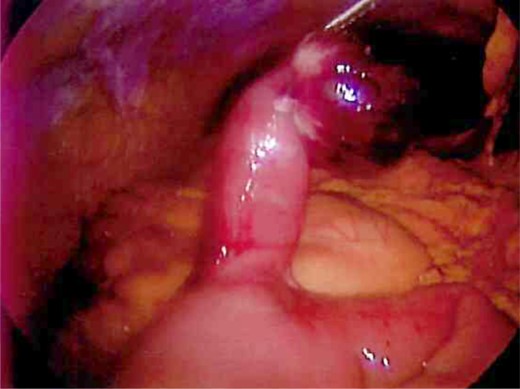

Laparoscopy was performed and a large Meckel's diverticulum was identified ∼30 cm proximal from the ileocecal valve. It had twisted 360° and was swollen and gangrenous at the distal half (Fig. 1). The tip of the diverticulum contained a 3-cm long mesodiverticular band that was attached to the mesentery of an adjacent loop of terminal ileum (Fig. 2). The mesodiverticular band was surgically divided, and the diverticulum was then de-torsed revealing a normal appearing base (Fig. 3). The diverticulum was excised along its base using an endoscopic stapler (Fig. 4). The surgery was completed with an appendectomy. On postoperative day one, the patient was doing well and was discharged home.

Excised Meckel's diverticulum before removal from the abdomen.